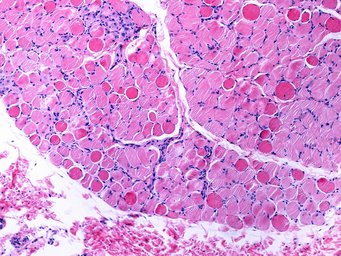

Bei der Duchenne Muskeldystrophie (DMD) handelt es sich um eine schwere Muskelerkrankungen, die vor allem Jungen betrifft. Die Erkrankung verläuft chronisch und beginnt bereits im Kindesalter. Die Lebenserwartung bei den betroffenen Patienten ist deutlich verkürzt. Verursacht wird die bislang nicht heilbare Erkrankung durch Mutationen im Dystrophin-Gen. Dieses liegt auf dem X-Chromosom. Dystrophin ist für die Stabilität der Zellmembran in Muskelfasern wichtig. Durch den Gendefekt fehlt den Patienten Dystrophin, so dass die Muskelzellen in ihrer Funktion eingeschränkt sind und die Muskulatur zunehmend geschwächt wird.

Die Max-Planck-Wissenschaftler zeigten nun an kultivierten Zellen von DMD-Patienten, dass die Dystrophin-mRNA-Fragmente in den Zellen eine verstärkte Produktion von Utrophin verursachen. „Der Mechanismus dahinter ist die transkriptionale Adaptation. Wenn man den Zerfallsmechanismus der Dystrophin-mRNA reguliert, kann man auf diese Weise die Produktion von Utrophin in den Zellen kontrollieren. Dies stellt einen Anknüpfungspunkt für eine Therapie dar“, so Falcucci.